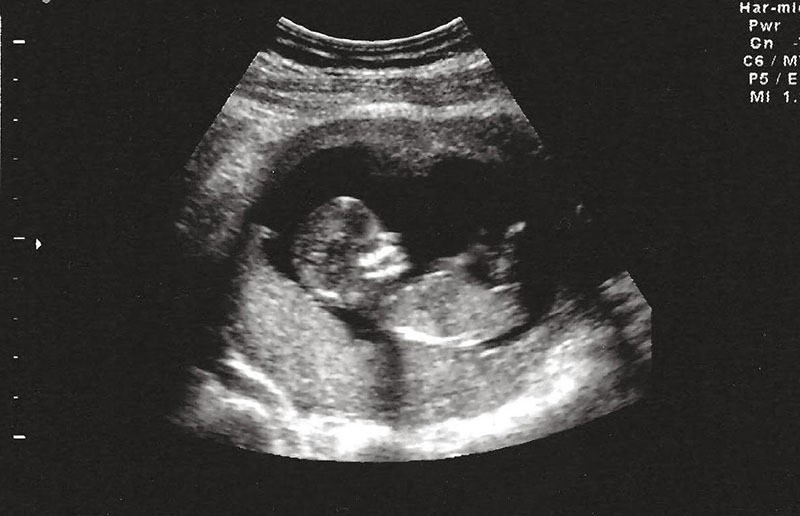

Ngày 23/2, Bệnh viện Nhi đồng 2 (TP.HCM) cho biết, các bác sĩ vừa phẫu thuật cắt bỏ khối u trong bụng bé gái 1 ngày tuổi. Trường hợp này được các bác sĩ gọi là thai trong thai hiếm gặp.

Bé gái sinh non 36 tuần nặng 3,4 kg tại Bệnh viện Từ Dũ (TP.HCM). Sau sinh, bé có biểu hiện bụng chướng căng, suy hô hấp.

Bé được chẩn đoán có khối u vùng bụng chưa rõ bản chất, tăng nhanh về kích thước. Vì vậy, bé được chuyển đến Bệnh viện Nhi đồng 2 điều trị.

Các bác sĩ ghi nhận khối u choán chỗ lớn trong ổ bụng thai nhi, bên trong có cấu trúc dịch, mô mỡ, nhiều cấu trúc dạng xương ống và xương dẹt, các mạch máu.